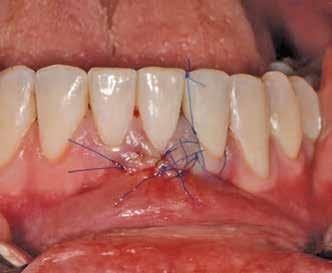

Az eljárást helyi érzéstelenítés mellett végeztük (4%-os articaine-hidroklorid 1:100 000 adrenalinnal). Papillakímélő, U alakú palatális bemetszést végeztünk, teljes vastagságú nyálkahártyalebeny preparálás történt, a lebenyt bukkálisan feltekertük (5. ábra). A lebeny bukkálisan feltekert részén de-epitelizációt végeztük el, amellyel kompenzálni tudtuk a bukkális lágyszöveti defektust. Szakaszos előfúrást végeztünk, és a bredent copaSKY 4x10 implantátumot 30 Ncm behajtási nyomatékkal helyeztük be (6. ábra). Az implantátumot 1 mm-re szubkresztálisan helyeztük be, hogy később szélesebb emergenciaprofilt tudjunk kialakítani (7. ábra). Az egyedi ínyformázó úgy készült, hogy kompozitot vittünk fel a titánbázisra, és így formáztuk a lágyszöveteket a transzgingivális gyógyulási fázis során (8. ábra). Az egyéni ínyformázó tulipán formájú, hogy kialakítsa a kívánt emergenciaprofilt. A lágyszövetet feszülésmentesen zártuk #6/0 nem felszívódó, monofil fonallal (Optilene, B. Braun Deutschland; 9. a–b. ábra). Posztoperatív röntgenfelvétel készült, ami alapján az implantátum a szomszédos fogakkal párhuzamos elhelyezést mutatott (10. ábra). Posztoperatív utasításokat adtunk a páciensnek a műtéti terület körüli szájhigiénia fenntartása érdekében. A beavatkozást követő egy héttel a varratokat eltávolítottuk, és a kezelt terület kielégítő gyógyulást mutatott (11. ábra). A 4 hónap utáni késleltetett terhelést a páciens kívánsága szerint terveztük.

1. ábra: Műtét előtti fogászati panorámafelvétel, amelyen a hiányzó felső állcsont jobb első premolárisát és a szabad véggel rendelkező hidat láthatjuk. — 2. ábra: Az implantátum méreteinek megtervezése CBCT-vel. 3. ábra: Bukkális lágyrészdefektus. — 4. ábra: A biológiai szélesség értékelése a vertikális lágyszövetvastagság alapján. 5. ábra: Palatinális „tekercslebeny” – Palatal roll flap. — 6. ábra: Bredent medical copaSKY 4x10 implantátumbeültetés. 7. ábra: Szubkresztális implantátumbeültetés a várható biológiai szélességnek megfelelően.

8. ábra: Egyéni ínyformázó titánbázison, tulipán alakú emergenciaprofillal. — 9. a. ábra: A sebzárás okkluzális nézete.